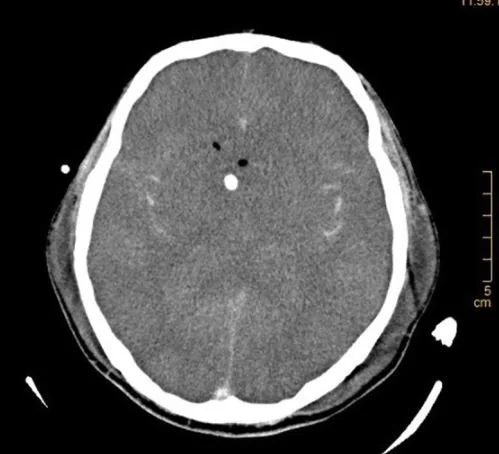

His CT is shown below.

What do you notice on the CT?

Our patient had increased intracranial pressure from Naegleria fowleri meningoencephalitis. His CT showed signs of increased intracranial pressure with absent ventricles and no gray-white differentiation.